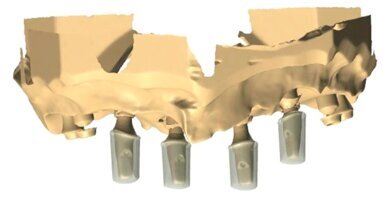

Po odsłonięciu implantu (Ryc. 10 i 11) rozpoczęliśmy kształtowanie profilu wyłaniania łącznikiem tymczasowym zespolonym z koroną tymczasową (Ryc.12). Na wizycie kontrolnej po założeniu korony tymczasowej stwierdziliśmy, że wskazana jest korekta girlandy dziąsłowej po stronie przeciwnej (Ryc. 13-16). Ryciny 17 i 18 pokazują dziąsło brzeżne nad implantem od strony przedsionka ukształtowane łącznikiem tymczasowym zespolonym z koroną tymczasową. Tak ukształtowany profil wyłaniania został zarejestrowany przy pomocy transferu wyciskowego zindywidualizowanego żywicą Patern Resin (Ryc.19). Transfer ten następnie użyłem w wycisku. Pozwoliło to technikowi doszlifować standardowy łącznik cyrkonowy do poziomu, na którym zaczyna on kontaktować z maską dziąsłową, tj. podpiera dziąsło pacjenta (Ryc. 21).

Docięty łącznik na modelu z maską dziąsłową laboratorium przekazało do gabinetu, gdzie następnie na modelu uzupełniłem żywicą przestrzeń pomiędzy łącznikiem a maską dziąsłową (Ryc. 22). Następnie przykręciłem łącznik wg klucza protetycznego w ustach pacjentki i nałożyłem na niego wcześniej przygotowany pierścień z żywicy podpierający dziąsło (Ryc. 23) i doszlifowałem go wiertłami wg standardów preparacji pod korony pełnoceramiczne (Ryc. 24-27). W pracowni pierścień ten został zeskanowany i wg niego zaprojektowano czapkę cyrkonową pod koronę ceramiczną (Ryc. 28 i 29).